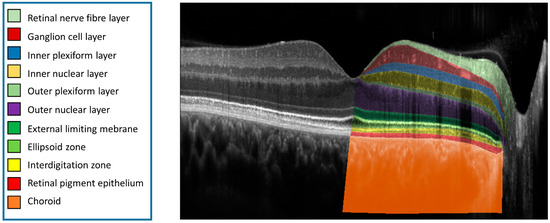

2.4. Image Layer Annotation